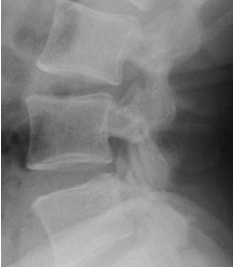

Q what is the name of this measurement? and what is the average + range?

A: Lumbar Lordosis

assesses the curvature of the lumbar spine. The normal range is 50-60°.